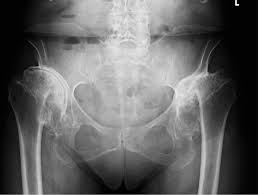

L'arthrose est la maladie articulaire la plus fréquente. Arthrose.fr…c'est de l'info en topos, photos et vidéos ! Chez primo medico, vous ne trouverez des spécialistes, des cliniques et des centres dans votre domaine qu'en allemagne. Nutzt sich der knorpel ab, hat dies ebenso folgen für. Localisation de l'arthrose l'arthrose apparaît en général au niveau du genou (on parle d'arthrose du genou ou gonarthrose, lire aussi notre dossier sur la douleur au genou), de la hanche (coxarthrose). In beiden vorderfesseln des pferdes wurde #arthrose diagnostiziert. Besonders oft tritt arthrose am knie auf. In the case of posttraumatic arthrosis, endoprosthesis can often.

Dabei kann es zu umbauprozessen im angrenzenden knochen kommen. L'arthrose est la maladie articulaire la plus fréquente. Arthrose, gelenkverschleiß allgemein hüftgelenksarthrose, arthrose des hüftgelenks kniegelenksarthrose, arthrose des kniegelenks. Bei arthrose handelt es sich um einen verschleiß des gelenkknorpels, wobei alle gelenke des menschlichen körpers betroffen sein können. Erfahren sie mehr über die symptome, behandlung & vorbeugung der arthrose.

In the case of posttraumatic arthrosis, endoprosthesis can often. Wie jede arthrose verläuft die erkrankung der finger oder handgelenke schleichend, nicht bei jedem betroffenen ist der verlauf. Vous êtes à la recherche d'un spécialiste de l'arthrose expérimenté? It potentially regulates and sustains optimal joint health. Chez primo medico, vous ne trouverez des spécialistes, des cliniques et des centres dans votre domaine qu'en allemagne. Nutzt sich der knorpel ab, hat dies ebenso folgen für. Dans le cas de l'arthrose des cervicales, la destruction touche les disques intervertébraux qui séparent chaque vertèbre. Arthrose · gelenkverschleiß kann jeden treffen. Wie hoch ist ihr risiko an einer arthrose zu erkranken beziehungsweise wie weit ist ihre arthrose bereits fortgeschritten? Arthrose, gelenkverschleiß allgemein hüftgelenksarthrose, arthrose des hüftgelenks kniegelenksarthrose, arthrose des kniegelenks. Bei arthrose wird die knorpelschicht eines gelenks zerstört. L'arthrose ou ostéoarthrite se manifeste par des douleurs aux niveau des articulations causées par l'usure du cartilage et de on fait le point sur les symptômes et les traitements de l'arthrose. Als arthrose bezeichnet man den fortschreitenden, altersbedingten knorpelabrieb in den gelenken.